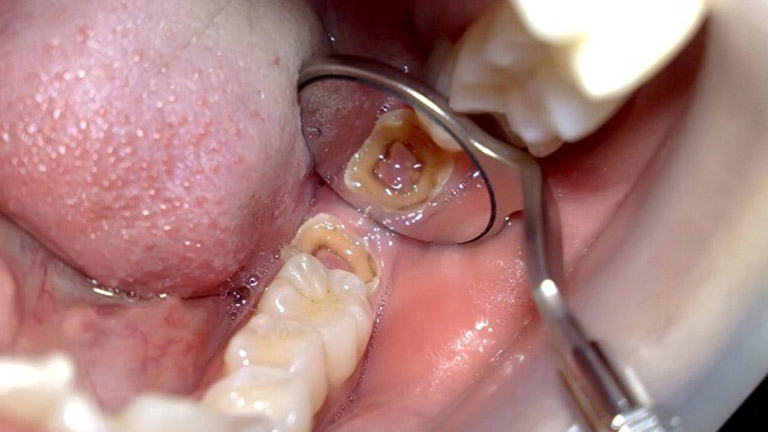

Nhổ răng khôn ở đâu an toàn tại quận Thanh Xuân Hà Nội